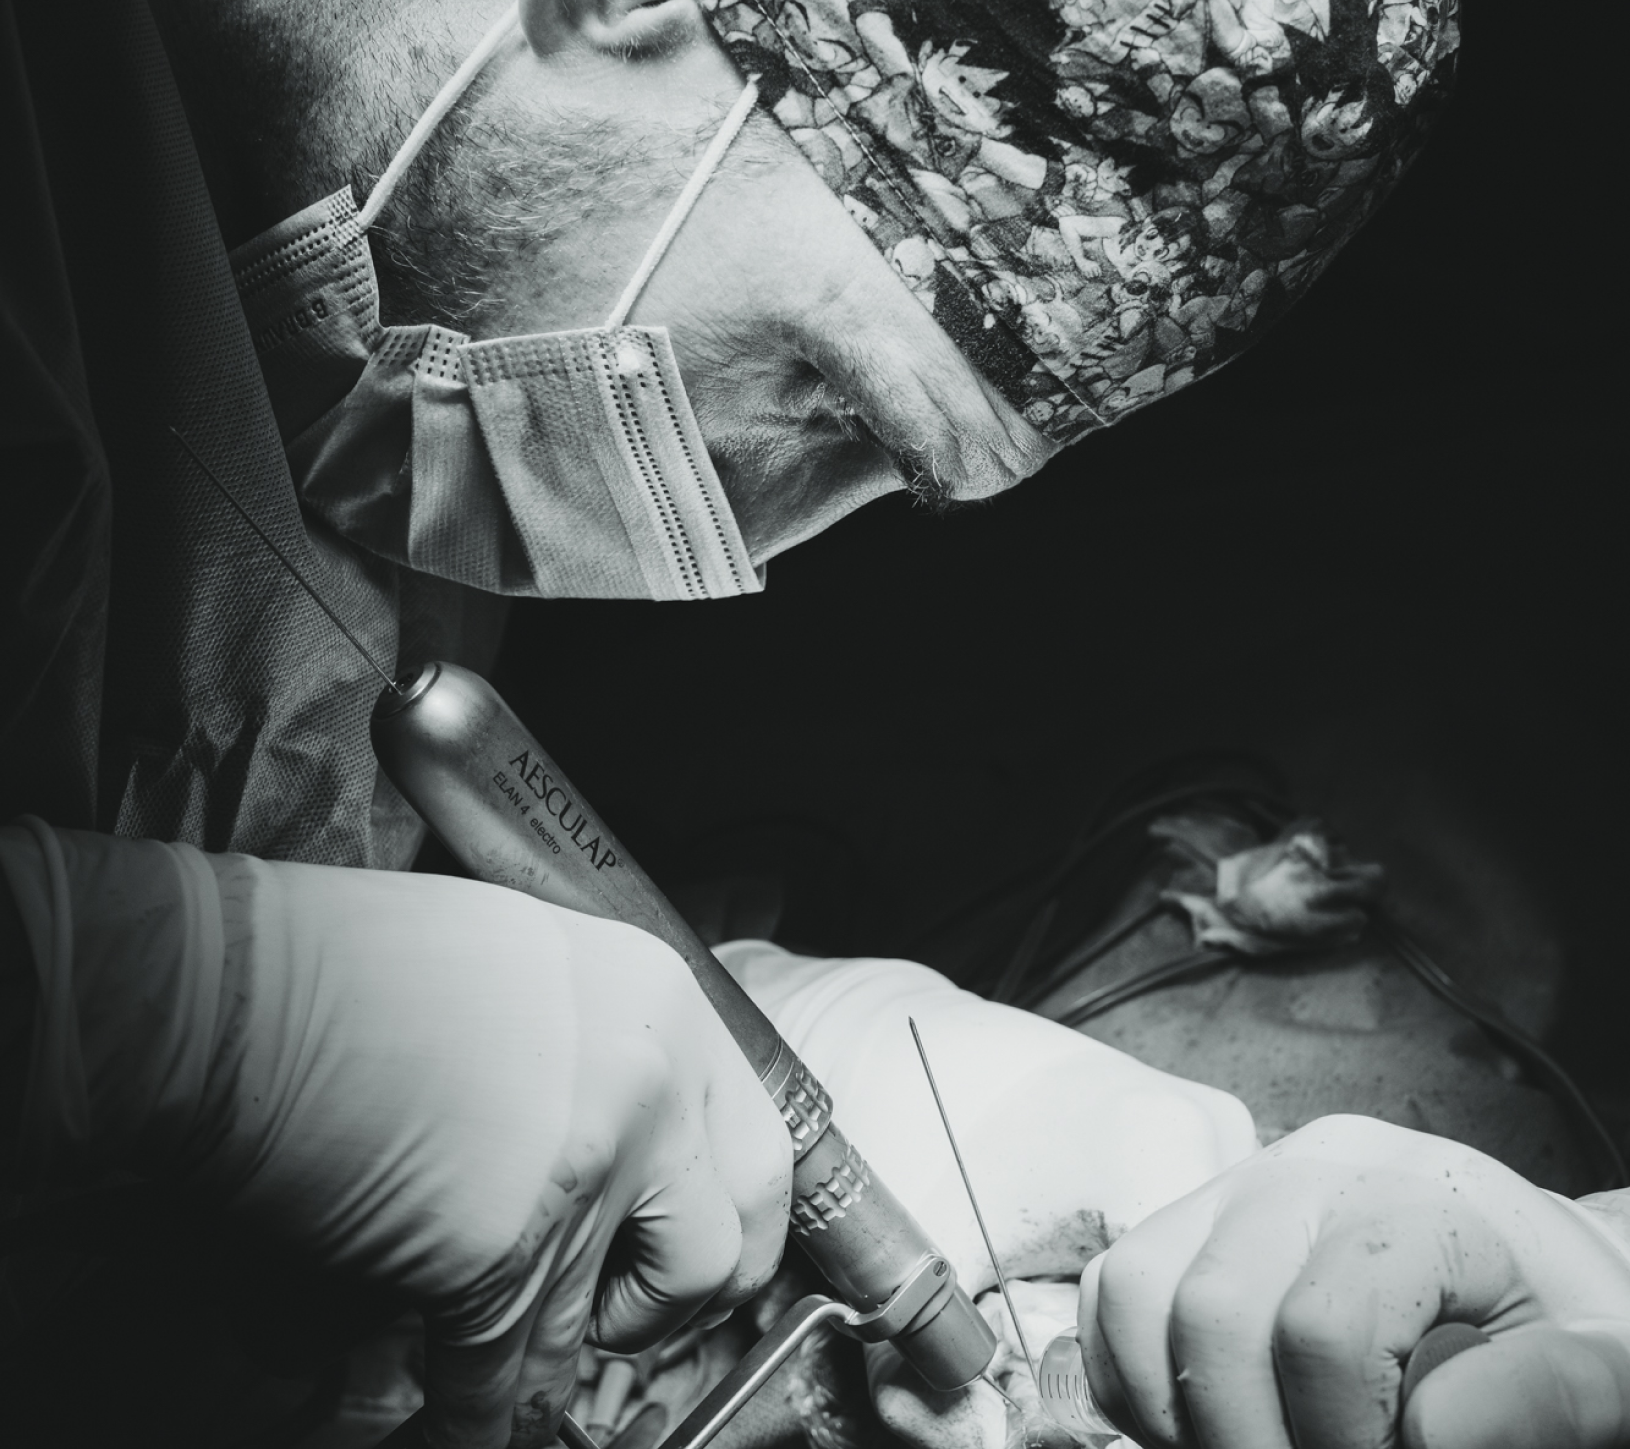

- Minimally Invasive Plate Osteosynthesis (MIPO): minimiza la invasion quirúrgica al reducir la necesidad de grandes incisiones y abordajes pero requiere de una evaluación y planificación prequirúrgica exhaustiva. Generalmente se realizan pequeñas incisiones en los tejidos próximos a los fragmentos óseos a estabilizar, y se procede a la reducción de la fractura, idealmente asistida por un fluoroscopio que garantice el óptimo alineamiento óseo. Habituamente se premoldea una placa de osteosíntesis que se desliza a través de las pequeñas incisiones creadas sobre los fragmentos de hueso y se fija a los mismos utilizando tornillos. En último lugar se suturan las incisiones creadas. La menor agresión quirúrgica puede favorecer una recuperación mas rápida y predisponer a menos complicaciones postquirúrgicas. Sin embargo, no todas las fracturas se pueden manejar mediante esta técnica.